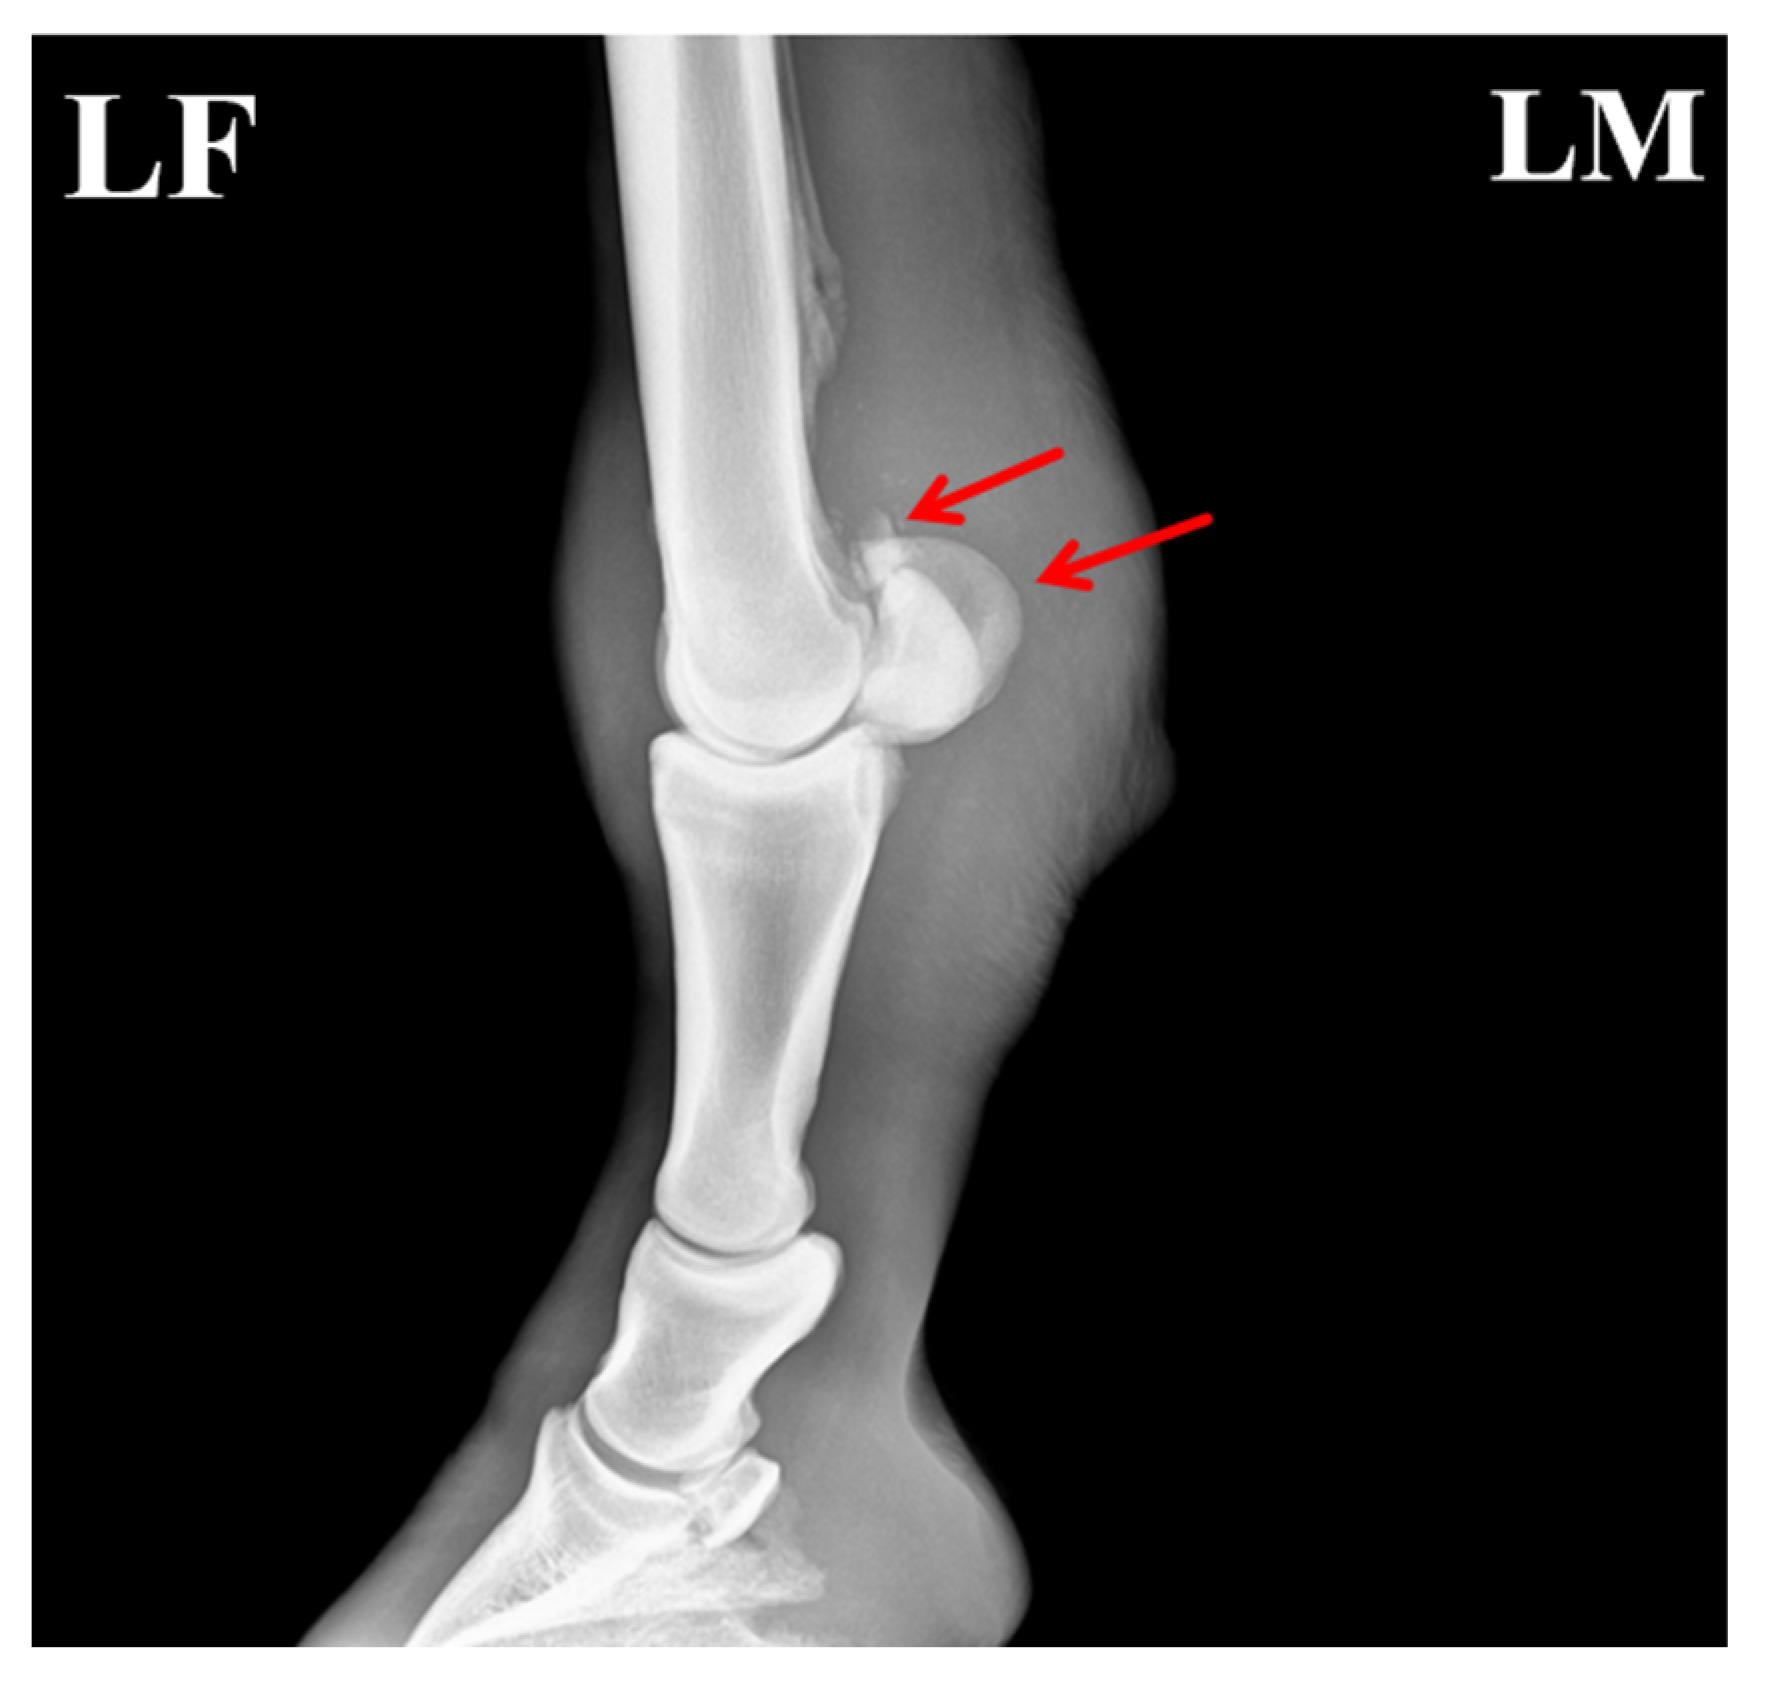

Due to the unique structure and function of the equine sesamoid bones, their healing process is typically more prolonged than that of other fractures. As shown in Figure 5, the proximal apex of the sesamoid bone exhibited a fracture with indistinct and blurred fracture margins, along with a localized area of increased soft-tissue density surrounding the fracture site. This homogeneous, cloud-like appearance indicated activation of the early repair response. Further imaging analysis revealed that the fracture gap was filled with a soft cartilaginous callus composed of collagen fibers and cartilaginous matrix synthesized by proliferating and differentiating fibroblasts and chondrocytes. This soft callus presented as a typical soft-tissue-density structure without signs of mineralization, and its contour conformed to the anatomical shape of the fracture ends, achieving initial bridging and stabilization of the fracture. Additionally, no significant bone resorption or necrosis was observed in the main fracture fragments. The gap between the small free fragment and the main sesamoid body had narrowed slightly compared with the pre-treatment images, with no evidence of displacement or malunion. These findings indicated that the healing process was in the critical stage of soft-callus formation, consistent with the physiological characteristics of sesamoid bone fracture repair in horses.

Figure 5. Post-treatment radiograph of the affected horse showing formation of callus at the fracture site. The arrows indicate the specific lesions.